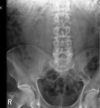

16

Ruptured AAA